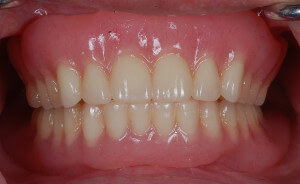

假牙在口內配戴狀況

DSC_3482

DSC_3481

完成的下顎活動假牙會有兩個墊圈,利用兩個橡皮墊的力量幫助假牙穩定